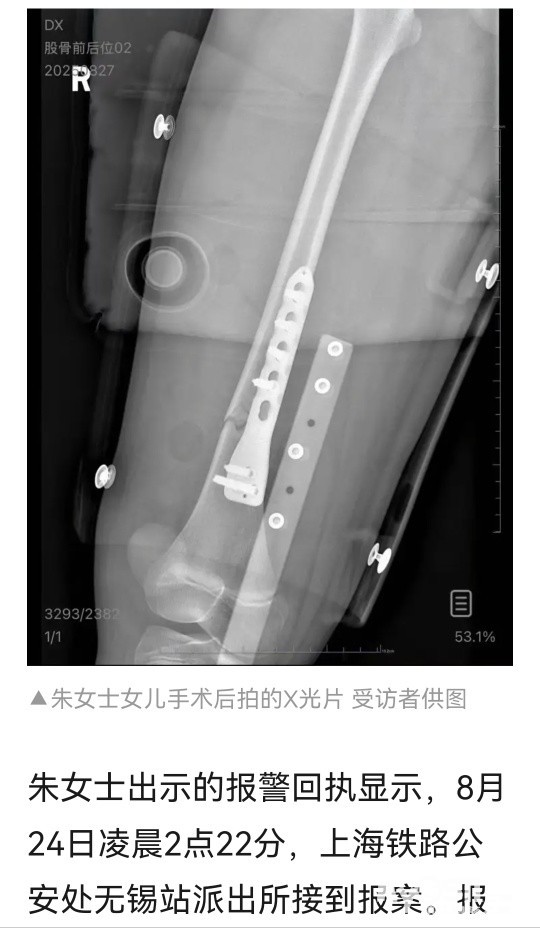

男乘客从列车上铺跌落砸伤10岁女孩致骨折,女孩母亲:他失去联系将通过法律程序维权